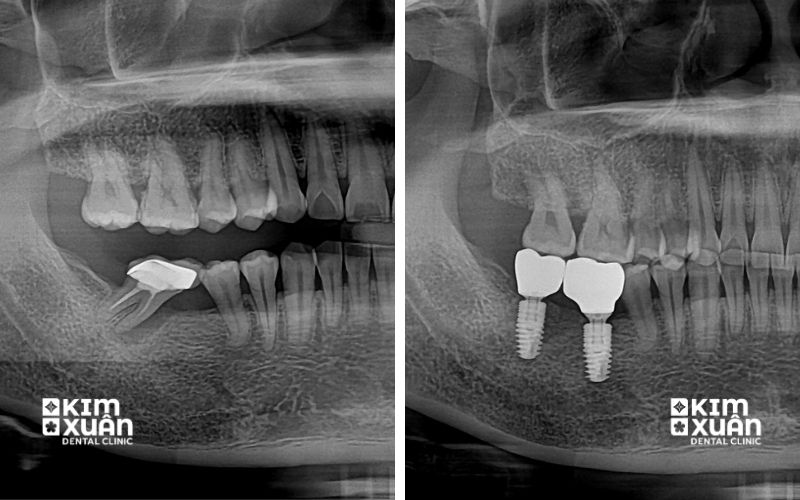

Mất răng lâu năm vẫn trồng Implant được. Có ngay cả khi răng đã mất trong thời gian dài và xảy ra tiêu xương hàm, trồng răng Implant cho người mất răng lâu năm vẫn là giải pháp phục hồi hiệu quả cả về ăn nhai và thẩm mỹ. Tuy nhiên, do xương hàm có thể bị tiêu nhiều, bác sĩ sẽ cần thăm khám lâm sàng và chụp phim CT để đánh giá mật độ xương, từ đó xây dựng phác đồ trồng Implant phù hợp.

Trong một số trường hợp, người mất răng lâu năm có thể cần thực hiện thêm ghép xương hoặc nâng xoang trước khi cấy Implant nhằm đảm bảo trụ Implant tích hợp chắc chắn với xương hàm và sử dụng bền lâu. Vì vậy, mất răng càng lâu càng nên trồng Implant sớm để hạn chế tiêu xương hàm nặng hơn, rút ngắn thời gian điều trị và đạt hiệu quả ăn nhai - thẩm mỹ tối ưu.

Mất răng lâu năm hoàn toàn có thể trồng lại được bằng phương pháp cấy ghép Implant. Đây là kỹ thuật phục hình hiện đại, trong đó bác sĩ đặt một trụ Implant vào xương hàm để thay thế chân răng đã mất, sau đó phục hình mão răng sứ bên trên.

Răng Implant sau khi hoàn thiện có hình dáng, màu sắc và chức năng ăn nhai gần giống răng thật, đồng thời giúp khôi phục thẩm mỹ khuôn mặt một cách toàn diện. Trong trường hợp mất răng đã lâu khiến xương hàm bị tiêu, bác sĩ vẫn có thể chỉ định ghép xương, nâng xoang hoặc ghép mô nướu trước khi cấy Implant để đảm bảo điều kiện phục hồi răng an toàn và bền vững.

Cấy ghép Implant là phương pháp phục hình hiện đại, có khả năng thay thế cả chân răng và thân răng đã mất. Trụ Implant được đặt trực tiếp vào xương hàm giúp ăn nhai chắc chắn, thẩm mỹ tự nhiên và ngăn ngừa tiêu xương hàm hiệu quả.

Vì vậy, cấy ghép Implant được đánh giá là phương pháp điều trị mất răng lâu năm hiệu quả và tối ưu nhất hiện nay. Trụ Implant thường được làm từ Titanium có khả năng tích hợp sinh học cao, giúp tạo lực nhai tương tự răng thật, kích thích xương hàm phát triển và duy trì cấu trúc khuôn mặt ổn định, lâu dài.